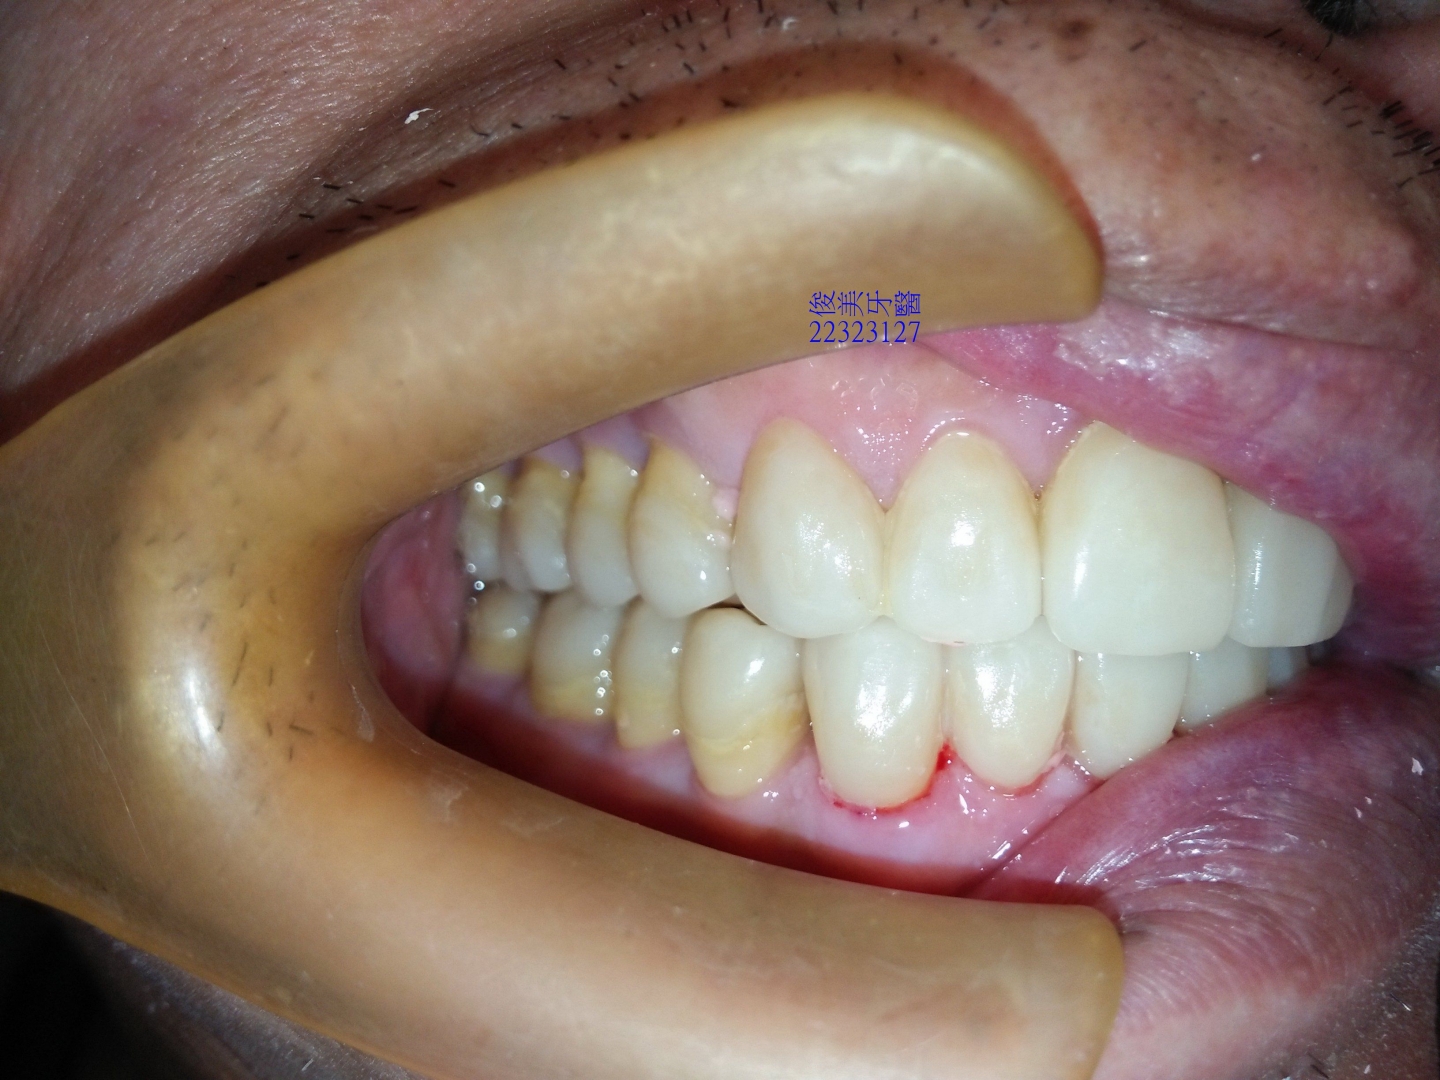

咬合狀況。

後牙高度已建立,恢復琺瑯質的厚度。